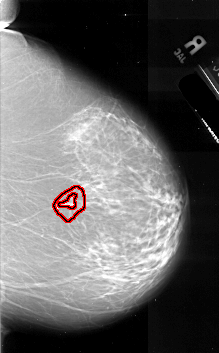

FILE: A_1070_1.RIGHT_MLO.OVERLAY

TOTAL_ABNORMALITIES 1

ABNORMALITY 1

LESION_TYPE MASS SHAPE IRREGULAR MARGINS SPICULATED

ASSESSMENT 5

SUBTLETY 2

PATHOLOGY MALIGNANT

TOTAL_OUTLINES 2

BOUNDARY

CORE